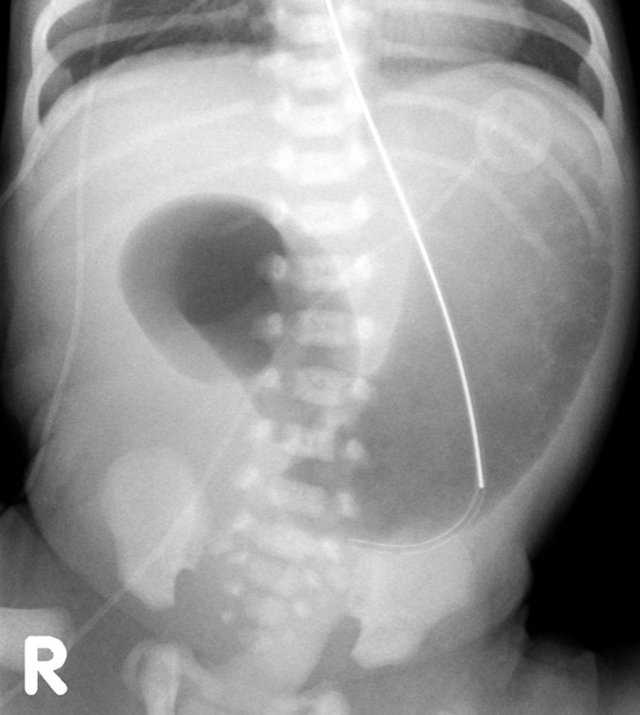

Study the image.

What are the findings and what is your diagnosis.

The findings are:

- Multiple dilated bowel loops indicating a distal obstruction.

- Bowel loop in the left groin

This was an incarcerated inguinal hernia.